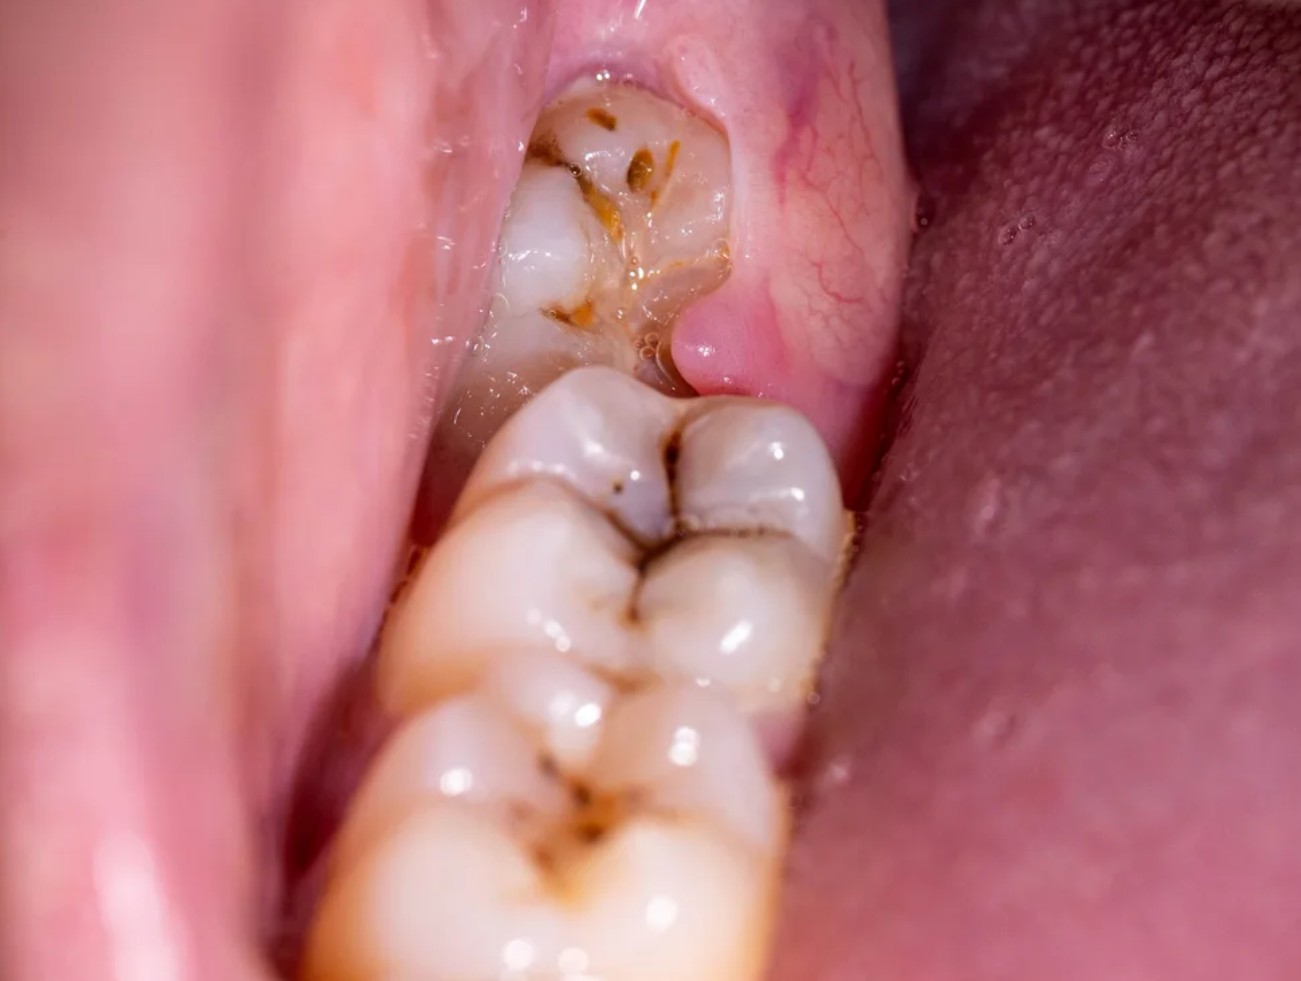

1. Dấu hiệu sắp mọc răng khôn

Khi răng khôn bắt đầu trồi lên, bạn có thể cảm nhận một số triệu chứng như:

- Đau âm ỉ vùng sau hàm, đặc biệt khi nhai.

- Nướu sưng, tấy đỏ hoặc xuất hiện cục lợi nhô lên.

- Cảm giác nặng, tức hoặc ngứa ở góc hàm.

- Đôi khi kèm theo đau đầu, mỏi hàm, sốt nhẹ.

Nếu các triệu chứng này kéo dài, rất có thể răng khôn đang mọc lệch hoặc bị kẹt dưới lợi.

2. Cách kiểm tra tại nhà

Bạn có thể soi gương để quan sát phía trong cùng của hàm:

- Nếu thấy phần lợi nhô cao, sưng đỏ hoặc thấy “mép răng” lộ ra, có thể răng khôn đang mọc.

- Tuy nhiên, nhiều răng khôn mọc ngầm sâu dưới nướu nên mắt thường không thể nhận biết.